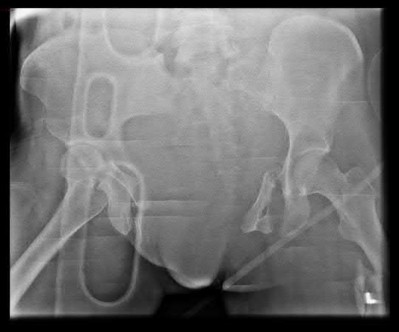

A 35 year-old female presents after prolonged extrication from a motor vehicle collision complaining of severe pelvic pain. Physical examination reveals diminished perianal sensation. She is otherwise neurologically intact. Figures A through D are radiographs and representative CT cuts of her injury. Which of the following nerve roots has likely been injured by the acute trauma?

The clinical scenario is consistent with a high-energy sacral fracture. The radiographs in figures A and B demonstrate a sacral fracture with posterior displacement of the right hemipelvis seen on the inlet view. Figures C and D are axial and sagittal CT images which show a displaced fracture of the right

hemisacrum along with a transvere fracture component through the S3 body . Diminished perianal sensation is concerning for an S2 nerve root injury.

Mehta et al reviewed the current management of sacral fractures. They note that the S1 and S2 nerve roots are more likely to be injured with sacral fractures as they occupy 1/3 to 1/4 of the neural foramina, as opposed to S3 and S4, which only occupy 1/6 of the neural foramina.

Robles reviewed the current literature to ascertain principles of evaluation and treatment for transverse sacral fractures. The author notes that injury to nerve roots S2 to S5 is manifested by impairment of urinary and anal continence and sexual function.